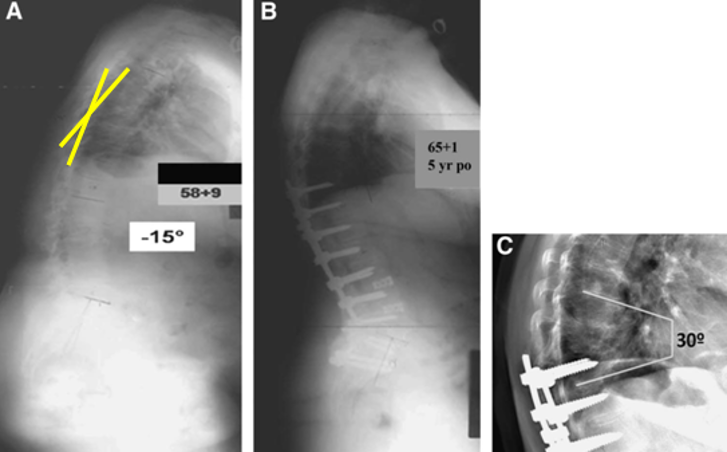

2)腰椎前凸(LL)过度矫正

图17 据文献报道,腰椎前凸(LL)过度矫正和SVA基线位置不当,均为增加PJK发生的风险因素

T10骨盆固定,出现交界性后凸

行翻修手术:T9/10SP截骨,延长到T4固定,预防性双侧肋骨固定(VEPTR)

图32-33 肋骨固定